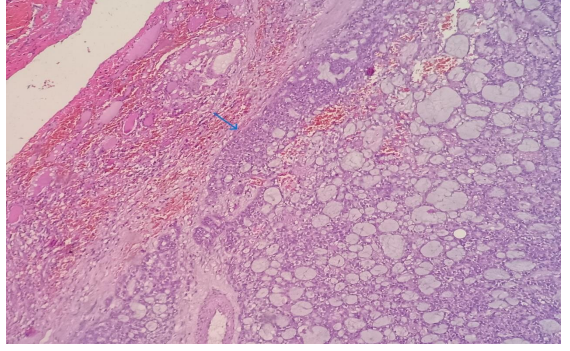

A 38 year old female presented with the complaints of pain and difficulty during swallowing and history of weight loss. Up on examination, a swelling was noted on the left side of her neck, which moved with deglutition. Ultrasound (USG) revealed a well circumscribed hypoechoic nodule measuring 3.2x2.1cm in the left lobe of thyroid with no extrathyroidal extension, however the nodule was compressing the esophagus. Fine needle aspiration was performed on the lesion and stained with Papanicolaou (PAP) stain and May Grunwald Geimsa (MGG) stains. The smears exhibited high cellularity with globoid clusters and three dimensional tissue fragments composed of aggregates of cells with central core of homogenous basement membrane material with cells having basaloid morphology and scant cytoplasm (Figure 2). MGG smears highlighted pink/ magenta amorphous basement membrane hyaline globules in the clusters of tumor cells (Figure 3). Cell block preparation of fine needle aspiration showed cribriform pattern of tumor cells with hyaline globules (Figure 4). Immunocytochemistry conducted on cell block shows TTF-1 positivity in normal thyroid follicles and negative staining in tumor cell clusters. CD117 and synaptophysin were inconclusive on cell block, but based on morphology this case was reported as adenoid cystic carcinoma of thyroid. Contrast-enhanced computed tomography (CECT) prior to surgery depicted a well defined heterogeneously enhancing hypodense lesion in the left lobe of thyroid measuring 3.2x2.1x1.7cm with no  additional lesions or abnormalities noted in the adjacent structures like trachea, larynx, oesophagus or upper mediastinum(Figure 1).  The excised left hemi-thyroidectomy specimen was received which showed a grey white solid homogenous lesion measuring 3.5x2.2x2cm reaching till the capsule. No cystic spaces/papillary projections/colloid seen in the lesion grossly. Adjacent thyroid parenchyma was normal. Histopathology sections showed tumor arranged in tubules and cribriform pattern along with hyaline globules suggesting the diagnosis of adenoid cystic carcinoma of thyroid, limited to thyroid without extra thyroid extension (Figure 5). IHC with CD117 showed cytoplasmic positivity in tumor cells further supporting the diagnosis (Figure 6).

Figure 1: Contrast-enhanced computed tomography of neck with well defined heterogeneously enhancing hypodense lesion in left lobe, limited to thyroid (arrow).